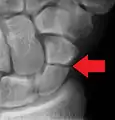

A subtle scaphoid fracture

A more obvious scaphoid fracture on a scaphoid view X ray

Radiolucency around a 12 days old scaphoid fracture that was initially barely visible.[13]